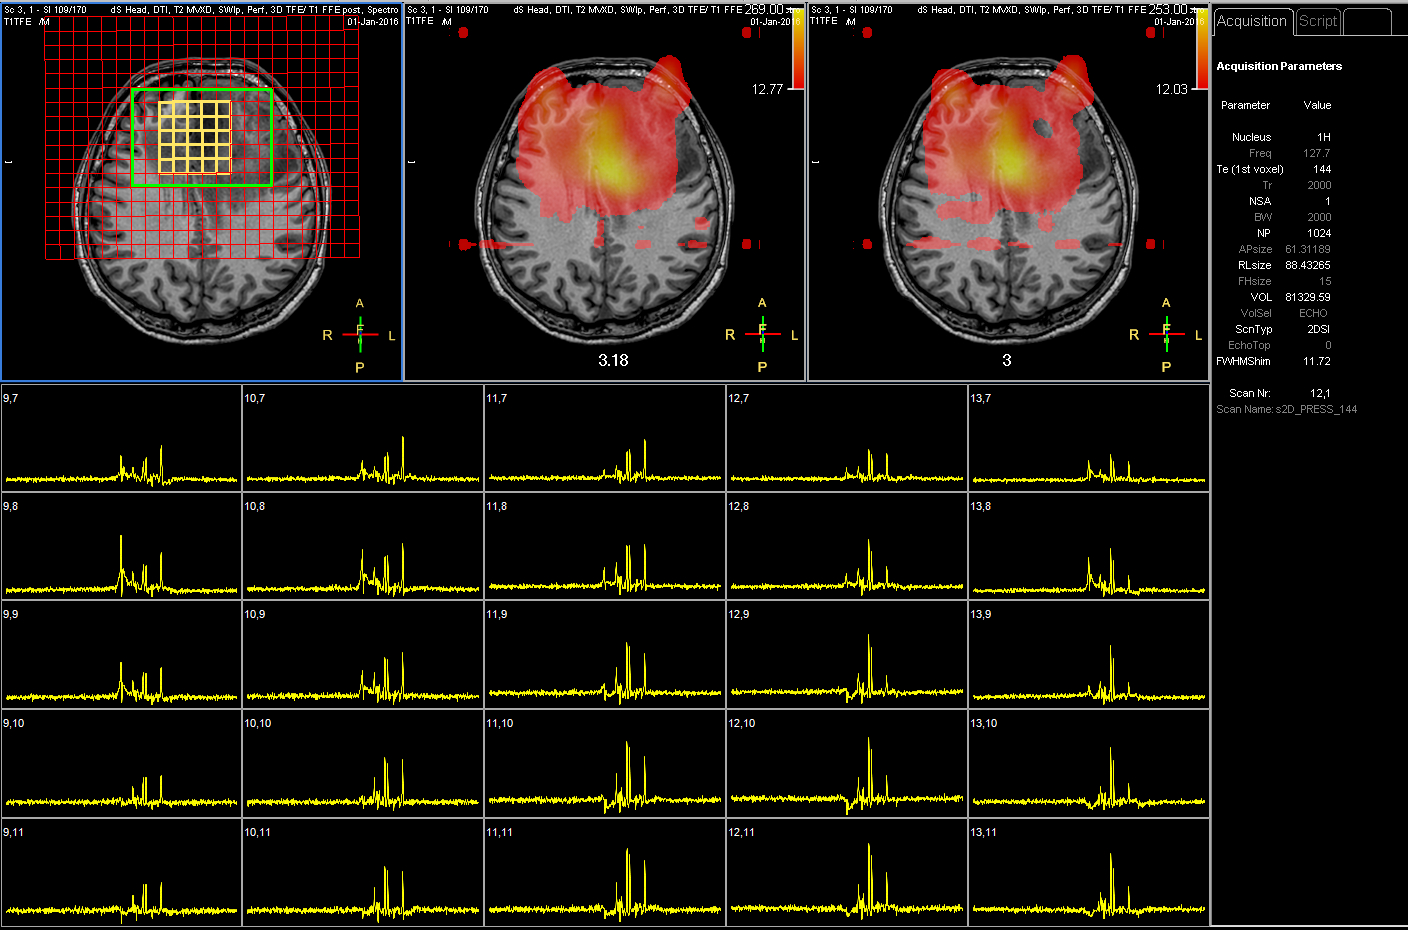

2D PRESS (TE 144)